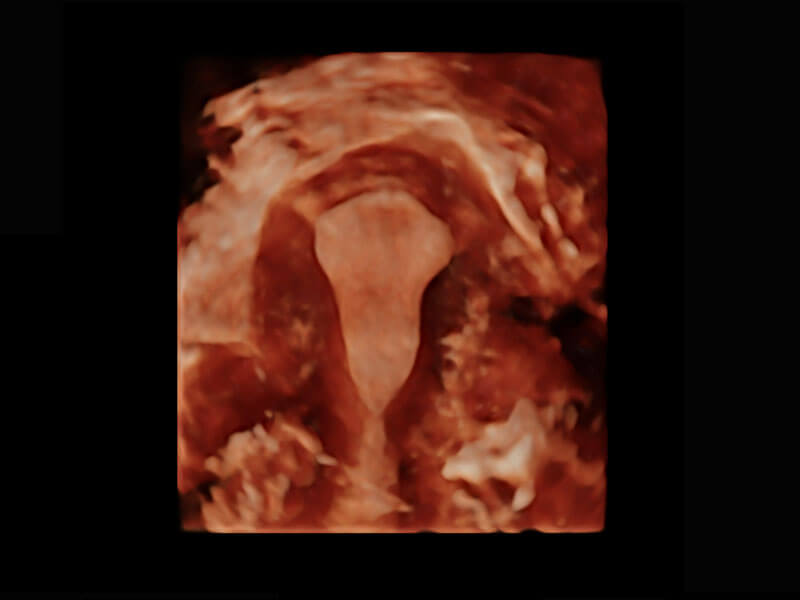

生殖健康

P60优异的图像质量搭载专科探头,在妇科基础疾病的诊断、卵泡生长的监测、输卵管通畅情况的判别等方面为您提供生殖应用方案。

• 腔内妇科-宫腔分离

• 腔内妇科-卵巢

• 腔内三维-宫内节育器

• 腔内三维-光影成像